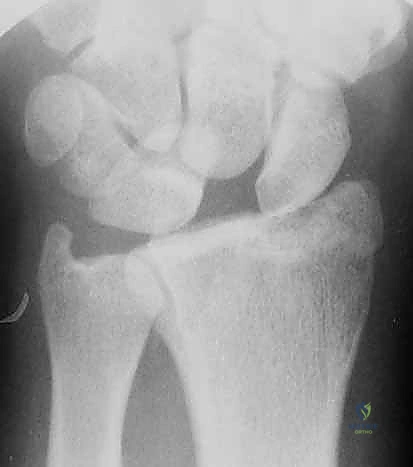

- الكعبرة البعيدة (Distal Radius): هي النهاية السفلية لعظمة الكعبرة (العظمة الأكبر في الساعد من جهة الإبهام). تشكل هذه العظمة الجزء الأكبر والأهم من مفصل الرسغ، وتتحمل حوالي 80% من القوة المنتقلة من اليد إلى الساعد.

أي كسر في هذه العظام، خاصة إذا امتد إلى داخل السطح المفصلي (Intra-articular fracture)، سيؤدي إلى اختلال الميكانيكا الحيوية للرسغ بأكمله. إذا لم يتم تسوية السطح المفصلي بدقة متناهية (بحيث لا يتجاوز الفارق 1 مليمتر)، فإن الغضروف سيتآكل بسرعة، مما يؤدي إلى ألم مزمن وخشونة مبكرة.

- كسور داخل المفصل (Intra-articular): الكسر يمتد ليشق السطح الغضروفي للمفصل (وهنا تبرز الأهمية القصوى لاستخدام المنظار).

يتم تحديد خطة العلاج من قبل الأستاذ الدكتور محمد هطيف بناءً على تقييم دقيق للصور الشعاعية (X-ray) والأشعة المقطعية (CT scan) لمعرفة مدى تفتت الكسر وتأثر السطح المفصلي.